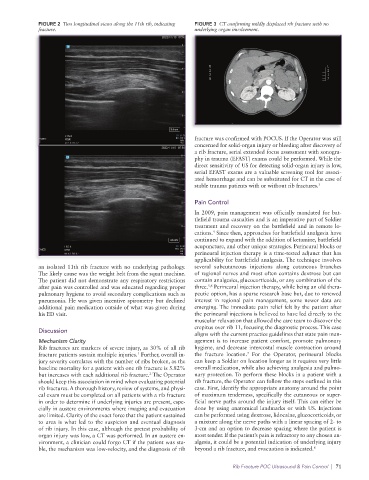

FIGURE 2 Two longitudinal views along the 11th rib, indicating FIGURE 3 CT confirming mildly displaced rib fracture with no

fracture. underlying organ involvement.

fracture was confirmed with POCUS. If the Operator was still

concerned for solid-organ injury or bleeding after discovery of

a rib fracture, serial extended focus assessment with sonogra-

phy in trauma (EFAST) exams could be performed. While the

direct sensitivity of US for detecting solid-organ injury is low,

serial EFAST exams are a valuable screening tool for associ-

ated hemorrhage and can be substituted for CT in the case of

stable trauma patients with or without rib fractures. 3